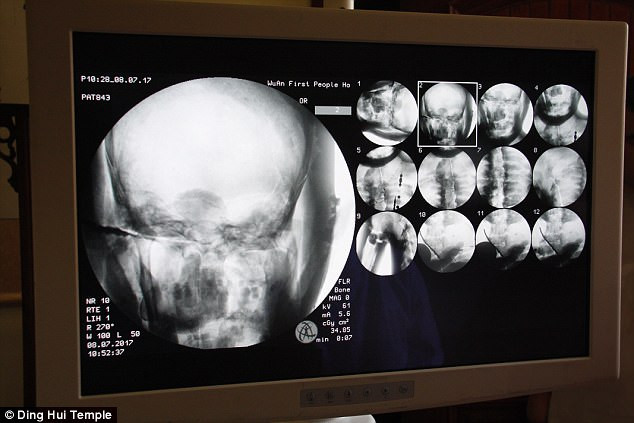

(Kiến Thức) - Các chuyên gia vô cùng bất ngờ khi tiến hành chụp cắt lớp vi tính xác ướp của vị đại sư Phật giáo sống cách đây 1.000 năm. Kết quả kiểm tra cho thấy bộ xương và sọ não của xác ướp còn nguyên vẹn một cách đáng kinh ngạc.

Các chuyên gia tiến hành chụp cắt lớp vi tính xác ướp đại sư Từ Hiền trước sự chứng kiến của các nhà sư, phật tử và phương tiện truyền thông.

Những người có mặt tại sự kiện trên đều vô cùng bất ngờ khi các chuyên gia thông báo thi hài đại sư Từ Hiền vẫn còn đầy đủ xương và sọ não hoàn chỉnh.

"Chúng ta có thể trông thấy xương cốt đại sư vẫn còn chắc khỏe như xương của người thường", bác sĩ Wu Yongqing chia sẻ.

Theo bác sĩ Wu Yongqing, xương hàm trên, hàm dưới, xương sườn, cột sống và tất cả khớp đều hoàn chỉnh. Điều này thật đáng kinh ngạc.